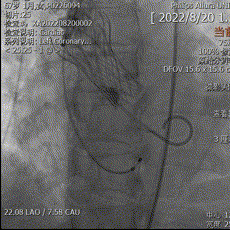

主动脉根部造影可见钙化影,采用18mm球囊预扩,有轻微腰征,无造影剂渗漏,左冠显影正常。

主动脉根部造影

球囊预扩